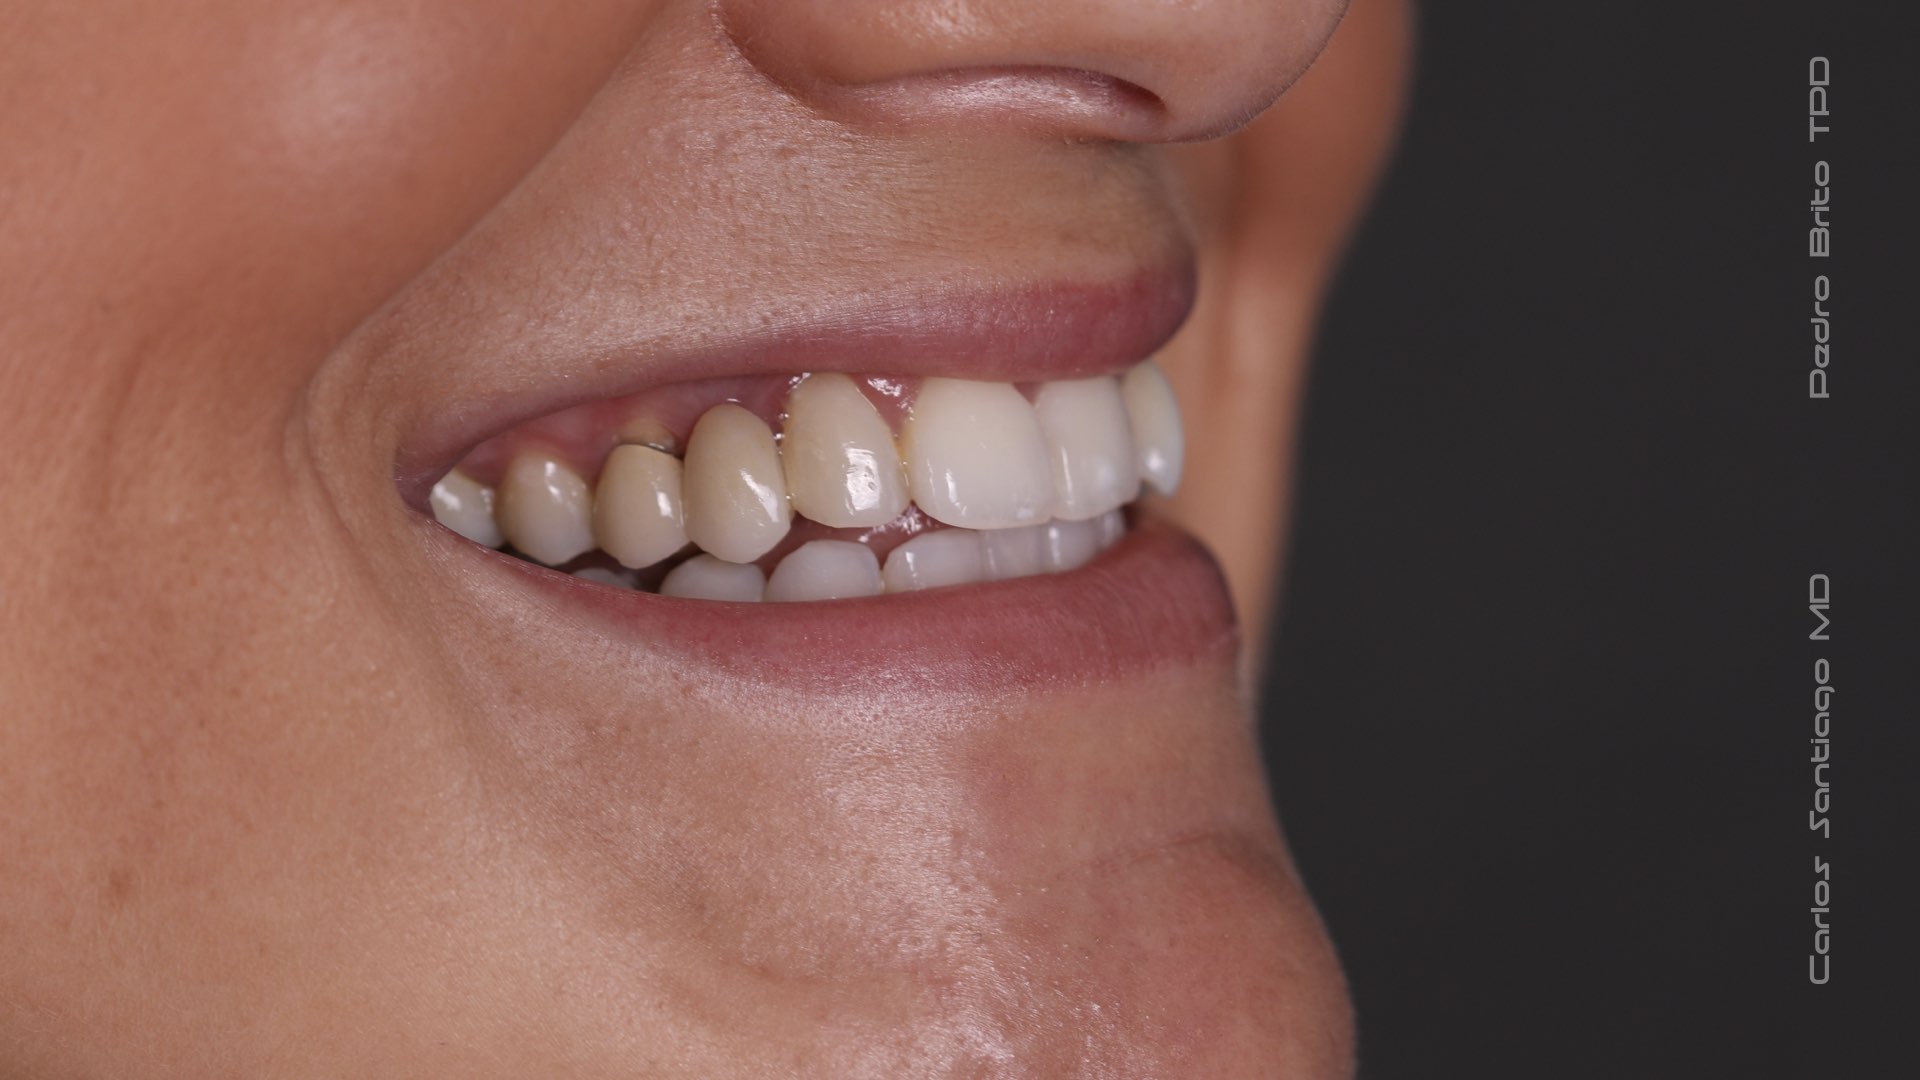

As Facetas Cerâmicas (lentes de contacto dentárias ou laminados), permitem corrigir da maneira mais estética e conservadora possível, problemas de forma e tamanho, côr e posição dos dentes, bem como substituir restaurações antigas e inestéticas.

São aderidas químicamente ao esmalte dentário de uma forma permanente, com o objectivo de melhorar a estética dos nossos pacientes.